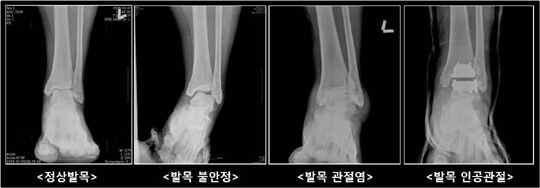

발목연골 손상과정

이렇게 치료하였음에도 불구하고 급성 발목염좌 환자 10~20%에서 만성 발목염좌가 발생한다. 장기적으로 만성 발목염좌가 지속되면 발목 불안정성이나 관절염을 초래하여 발목 고정술이나 인공관절 치환술과 같은 수술이 불가피한 상황으로 발전될 수 있다. 그러므로 급성으로 발목염좌가 발생하여 수일이 지나도록 부종이나 통증의 호전이 없다면 병원에 내원하여 적절한 치료를 받아야 한다.